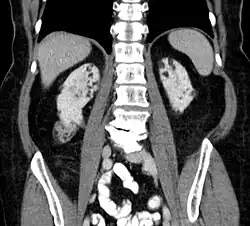

Computed tomography showing multiple angiomyolipomas of the kidney in a patient with lung lymphangioleiomyomatosis on CT: suspected TSC

Between 26% and 80% of TSC patients have benign tumors of the kidneys called angiomyolipomas, with hematuria being the most frequent presenting symptom. [8] TSC angiomyolipomas differ from non-TSC angiomyolipomas in age of presentation (31.5 years vs 53.6 years), mean tumor size (8.2 cm vs 4.5 cm), and percentage of cases requiring surgical intervention (50% vs 28%).[8] Although benign, an angiomyolipoma larger than 4 cm is at risk for a potentially catastrophic hemorrhage, either spontaneously or with minimal trauma.